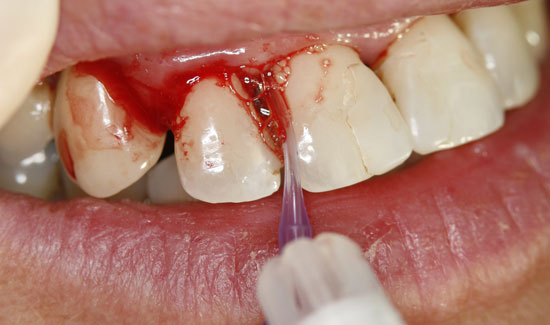

As an ozone gas source, we used Prozone, which, with the aid of plastic attachments, makes it possible to introduce ozone gas into the pockets in a pain-free manner. The local application of ozone gas was repeated three times, at weekly intervals. The patient was also made aware of necessary personal hygiene measures. Not only were we able to stop the bleeding, but we were also able to keep the degree of mobility of the teeth at a stable level (2) and reduce the measurable depth of the pockets.

Fig. 3: Condition after ozone therapy. Chlorhexidine staining of the teeth

Fig. 2: Clinical aspect of region 12, formation of gas bubbles on the inflamed tissue. Continuous suction in the vicinity of the area of use